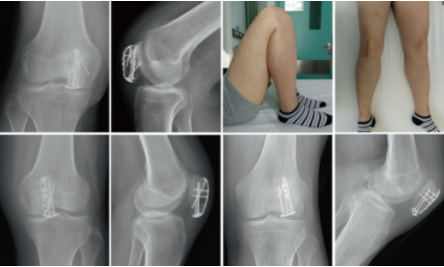

图3. 一名53岁男性因摔伤致左侧髌骨下极骨折。

a-b术前三维CT;术后第2天患肢膝关节.

c-d正、侧位x线片;术后1年复查患者膝关节前、侧位x线片;术后1年复查膝关节功能。

图4. 46岁女性髌骨远端骨折患者。

a-b术前膝关节三维CT和侧位x线片;术后第2天患肢膝关节

c-d正、侧位x线片。